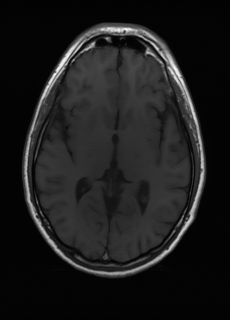

As we observe from the right image in Fig. 2, our BRM, both from MIMO and SISO settings, predicts the performance of dedicated models with a high correlation. We further choose the best three , and perform the last stage of fine-tuning accordingly to (6). A visual evaluation on real data is shown in Fig. 3. For simulated data, please refer to the Supplemental Material section.

Base on the best performing , we perceive that among , , and FLAIR, the results are best when is sampled the most. We suggest that this makes intuitive sense as images provide the best contrast out of the three sequences, which can compensate for the details lost in other images. The same observation can be made on the simulated data, where both and FLAIR show good contrast. When the time setting is changed to non-uniformity, we can see that our search for the best sampling strategy reflects the change. is sampled more as a result of faster acquisition time, while is still sufficiently sampled.